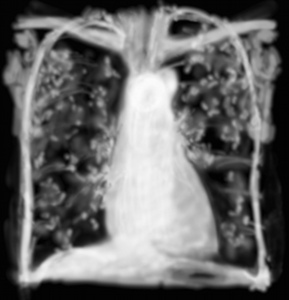

RP lymphangite carcinomateuse

La lymphangite carcinomateuse est une infiltration interstitielle diffuse linéaire par épaississement des lymphatiques des septas interlobulaires.